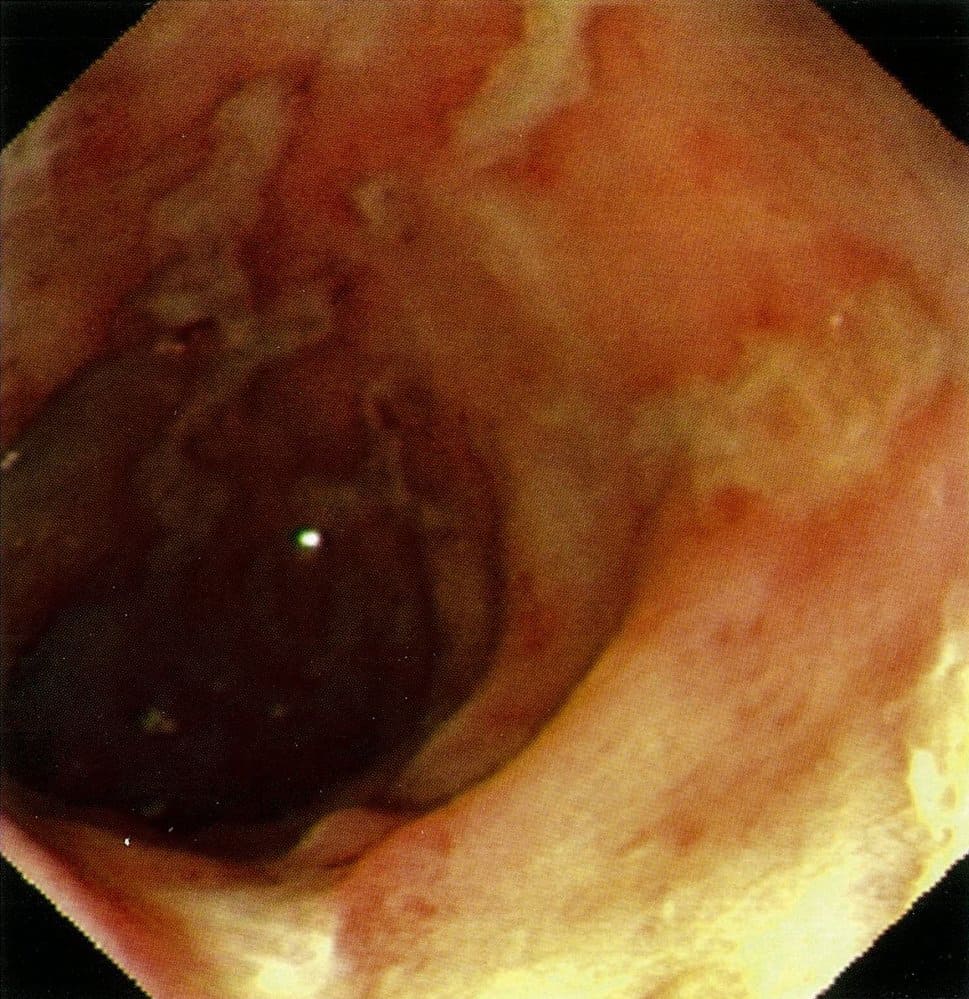

بیماری کرون

بیماری کرون (CD) نوعی بیماری التهابی روده (IBD) است که پاتوژنز آن کاملاً شناخته نشده است. تظاهرات بالینی CD ممکن است مشابه کولیت اولسراتیو (UC)، دیگر بیماری شایعِ IBD باشد. کرون بیشتر در بزرگسالان جوان و نوجوانان در سنین ۱۵ تا ۳۵ سالگی دیده میشود. این بیماری به طور معمول ایلئوم انتهایی را تحت تأثیر قرار میدهد، اما میتواند به طور متناوب کل دستگاه گوارش را تحت تأثیر قرار دهد و معمولاً منجر به عوارضی مانند فیستول، آبسه و تنگی روده میشود.